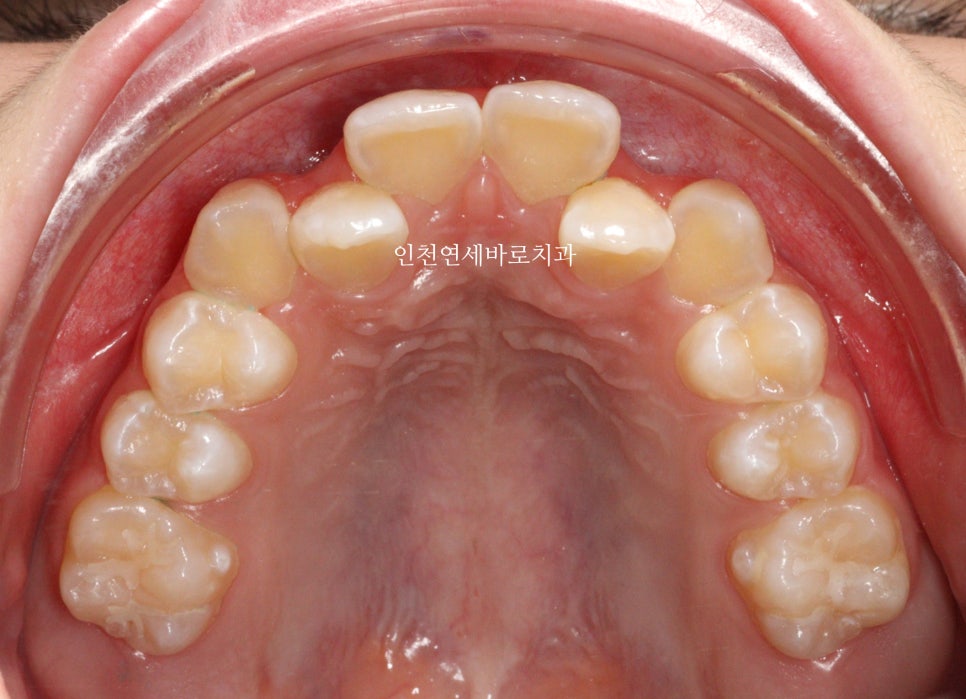

두번째 치아가 덧니로 있는 경우의 치료는 흔한 경우지만

생각보다 많은 노하우가 필요한 치료라고 생각합니다.

교정 치료 중에 화살표 최후방 치아가 맹출하여,

이 치아를 배열하는 과정에서 치료가 조금 더 길어지긴 했습니다

최후방 치아가 나올때 약간 삐뚤게 나옴으로 인해 1회 재제작을 했습니다.